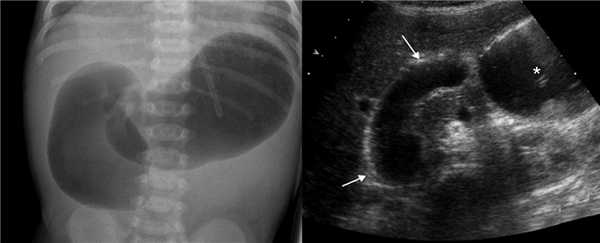

При незавершенном повороте брюшинные тяжи натянуты над 12-ти перстной кишкой и могут вызывать дуоденальную обструкцию, тогда желудок и проксимальный отдел 12-ти перстной кишки расширены. На рентгене определяются два газовых пузыря с уровнем жидкости. Полная обструкция характерна для атрезии, тогда газ в нижележащих отделах кишечника отсутствует. При незавершенном повороте чаще встречается неполная обструкция, тогда определяется газ в нижележащих отделах кишечника. На УЗИ после кормления определяют две заполненные жидкостью полости — желудок (звездочка) и проксимальный отдел 12-ти перстной кишки (стрелки).

Рисунок. Новорожденный с подозрением на высокую кишечную непроходимость. На рентгене и на УЗИ знак двойного пузыря. Во время операции определили незавершенный поворот с брюшинным тяжем над 12-ти перстной кишкой.

Первичные жалобы нередко заставляют пациента обратиться за консультацией гастроэнтеролога. После клинического осмотра и диагностики заворота кишок пациент направляется в хирургический стационар. Диагностику осуществляет абдоминальный хирург. При завороте сигмовидной кишки обзорная рентгенография выявляет увеличенную в размерах кишку, верхняя граница которой может доходить до диафрагмы. Четко видны два уровня жидкости - в проксимальном и дистальном отделах кишечника.

При завороте слепой кишки в правой половине брюшной области определяется округлая, перераздутая гаустрированная петля, ширина горизонтального уровня жидкости может достигать 20 см. В случае перекрута петель тонкой кишки в ней также определяются множественные уровни жидкости; дистальный отдел кишечника узкий, спавшийся. При рентгенографии пассажа бария по тонкому кишечнику отмечается задержка контраста на уровне заворота, отсутствие контраста в толстой кишке через 6-12 часов от начала исследования.